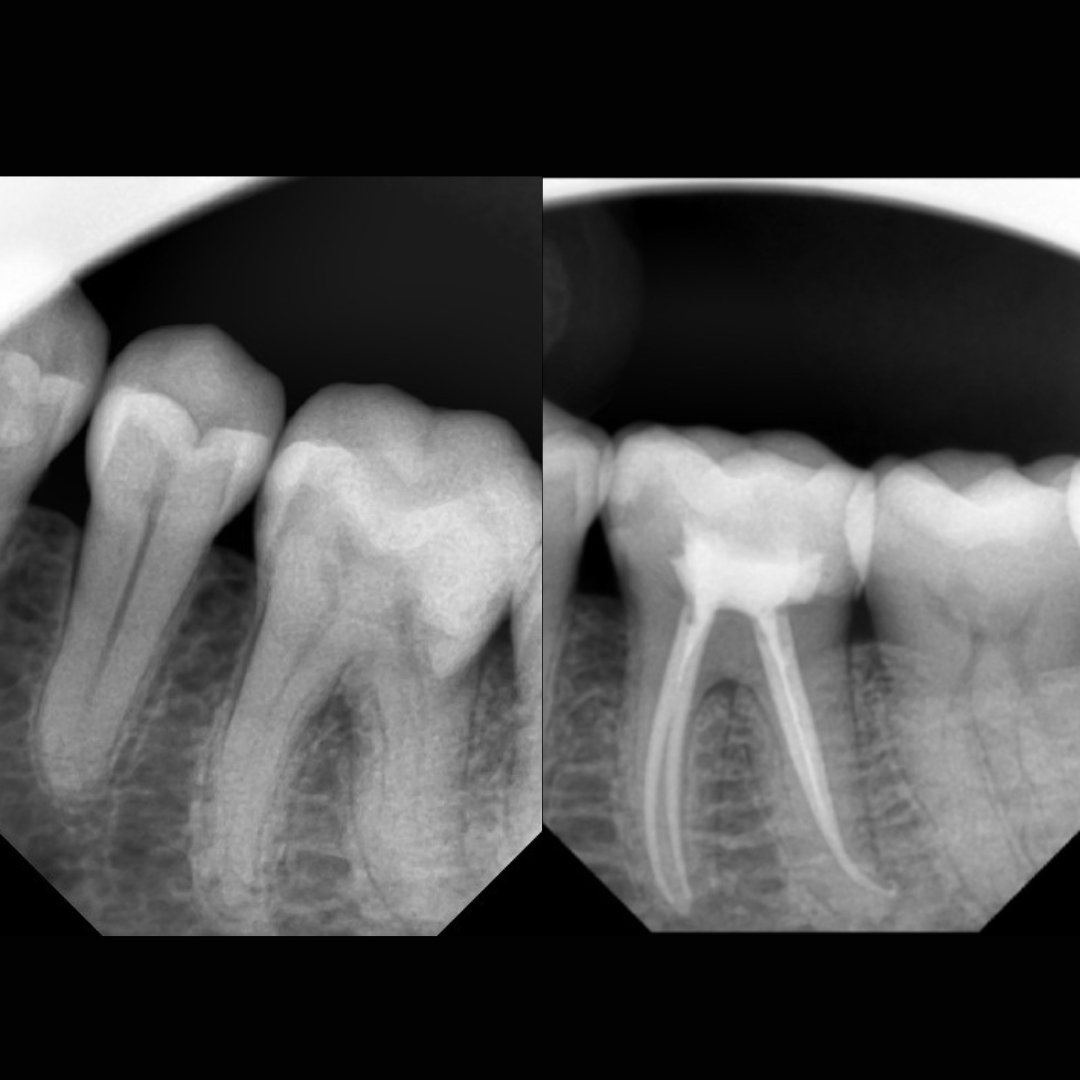

Before After Perawatan Saluran Akar (PSA) di Klinik Utama Pondok Gigi Jakarta

Transformasi nyata setelah perawatan saluran akar (PSA) di Klinik Utama Pondok Gigi Jakarta. Dari gigi rusak dan nyeri hingga kembali sehat dan berfungsi normal. Dikerjakan oleh dokter gigi profesional dengan teknik endodontik modern dan alat berteknologi tinggi untuk hasil maksimal.